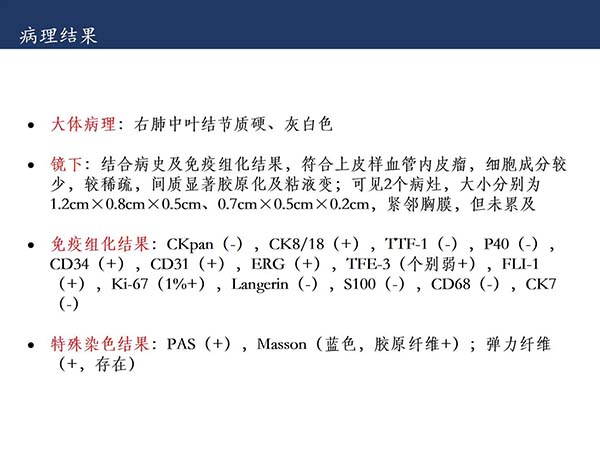

【杨柳科普】肺上皮样血管内皮瘤的影像表现